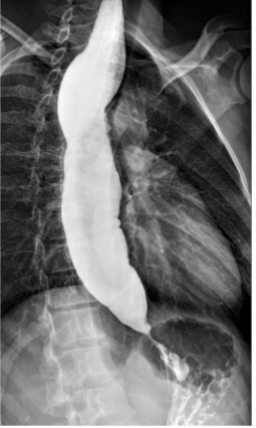

What is this and what type of scan

Varices, Barium swallow